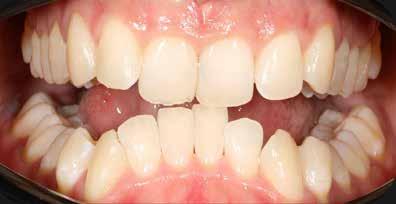

Általánosan elmondhatjuk, hogy a fogszabályozó kezelés iránt érdeklődő páciensek az első konzultáció során elsősorban az esztétikai kívánalmaiknak adnak hangot, és ritka az olyan eset, amikor a funkcionális problémák kerülnek előtérbe a részükről.

Nagyon fontos, hogy a modern arc- és mosolyesztétika által vezérelt fogszabályozási elvek alkalmazásával – minden esetben – az esztétikai céloknak megfelelően kerüljön megvalósításra az okklúziós korrekció.

A természetes mosoly tervezésénél az alábbi esztétikai paramétereket kell figyelembe vennünk:

1. A mosolyvonal megfelelő íves lefutása;

2. A felső metszőfogak teljes vertikális láthatósága;

3. Az íny ideális láthatósága (hölgyeknél 1-2 mm, férfiaknál 0-1 mm);

4. A felső fogív megfelelő szélessége. A cél a 10 vagy 12 fogas mosoly, második premoláristól második premolárisig, vagy első nagyőrlőtől első nagyőrlőig;

5. A felső középső metszők antero-posterior pozíciója a felső

A 28 éves hölgypáciens is elsősorban a szép mosoly elérésének igénye miatt szeretett volna fogszabályozást, bár tudomása volt a mélyharapásáról (1–5. képek).

A kezelési célokat a fogívek tágítása a megfelelő mosolyszélességhez és az alsó frontfogak torlódásának feloldásához, valamint a mélyharapás és a kismértékű disztálharapás korrekciója jelentették (6–11. képek).

Passzív önligírozó fix fogszabá-

lyozó készülékkel 15 hónapig tartott a kezelése. Az ilyen mélyharapásos esetekben nagyon fontos, hogy a harapásemelésnél nem történik intrúzió a felső fogíven, mert az kifejezetten negatívan befolyásolná a vertikális mosoly-display-t! A fogszabályozó kezelés után, ahogy az általában lenni szokott, a bölcsességfogak eltávolításra kerültek. Mint minden esetben, a fogszabályozás aktív fázisa után a retenció, a passzív helyben tartó fázis a kezelési eredmény megtartásához rendkívül fontos!